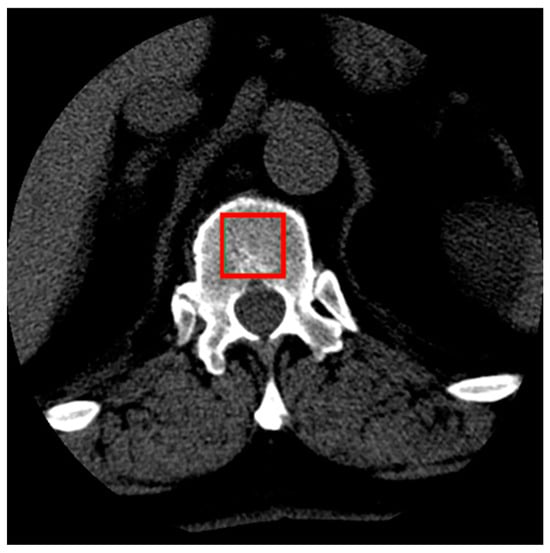

Sample cross-sections from the series of images were selected, showing the interior of the vertebra along with the cancellous bone. From each patient’s series of scans, four cross-sectional images of the L1 vertebra were selected. These images represented cross-sections closest to the midpoint of the vertebra’s height to ensure that the largest possible area of cancellous bone was visible (Figure 1). From each selected cross-sectional image, a single sample of the examined tissue image was obtained.

Figure 1. Illustration of the selection of cancellous bone tissue area for the study (red box).